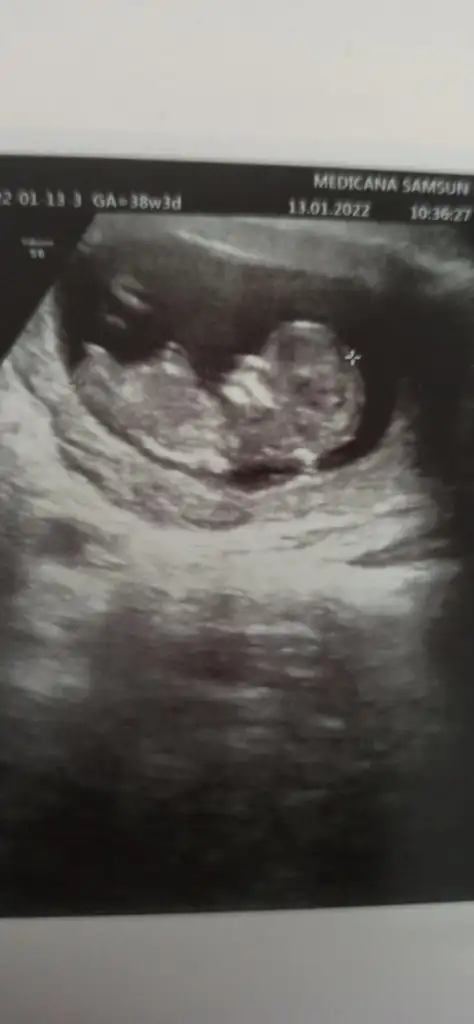

Merhaba tebrik ediyorum bildiniz kızım olacakKız gibi sanki en iyi 11 12 13 haftalar olmalı

Erkek gibi sanki emin olamadımCinsiyet tahmini alabilir miyim lütfen çok merak ediyorumIkra meyra

Erkek gibi sanki